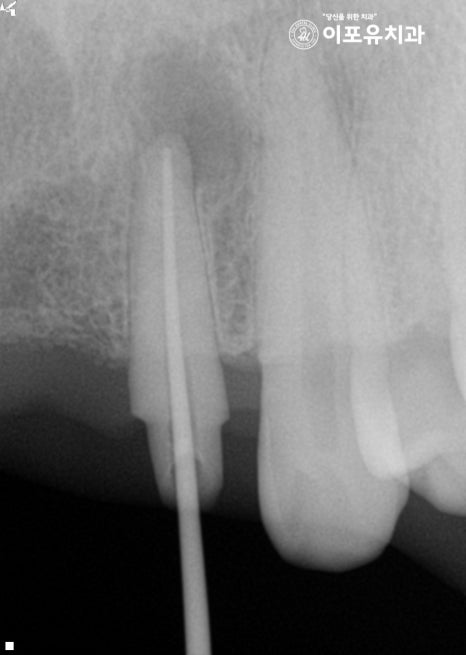

근관 내부를 깨끗하게 청소한 뒤

소독과정까지 확실하게 마쳐야 됩니다.

이후 충전재를 사용하여 뿌리 끝까지 밀폐하여

2차 감염의 확률을 줄여줍니다.

여기서 꼭 확인해야 될 것이 있습니다.

과정이 모두 끝났다 해서 다가 아닙니다.

꾸준한 추적 관찰을 통해 확실하게 사라졌는지

확인을 하는 것이 좋은 방법이죠.